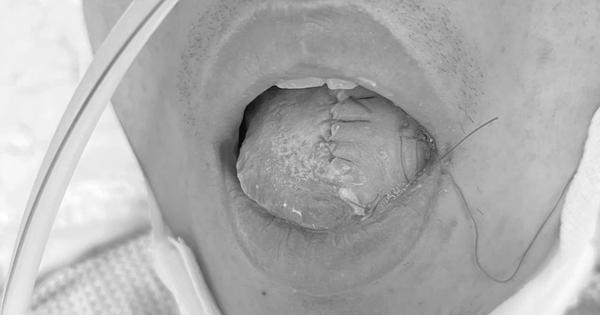

Tái tạo lưỡi cho nam thanh niên mắc ung thư lưỡi